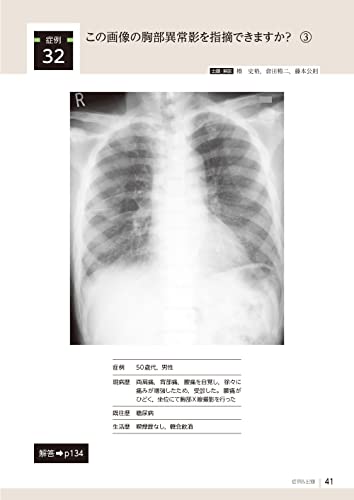

32 Can you identify the abnormal chest shadow in this image? ③ 41